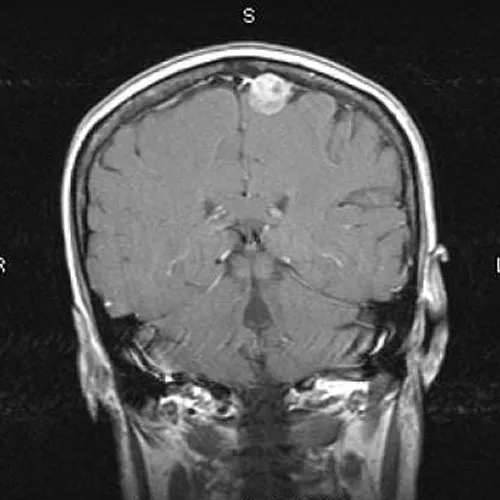

Metástasis cerebrales

Es considerada una complicación común en pacientes con cáncer avanzado y se estima que alrededor del 20-40% de los pacientes con cáncer desarrollarán metástasis cerebrales en algún momento de su enfermedad.

Gliomas cerebrales

Son un tipo de tumor que se origina en las células gliales del cerebro. Las células gliales son responsables de brindar soporte y nutrición a las neuronas y desempeñan un papel importante en el funcionamiento normal del sistema nervioso central.

Meningioma

Son tumores cerebrales que se originan en las meninges, las membranas que cubren el cerebro y la médula espinal. Estos tumores son generalmente benignos, lo que significa que no se propagan a otras partes del cuerpo, aunque en algunos casos pueden volverse malignos.

Cirugía Neurológica Radiocirugía/cirugía de Columna

16 años de experiencia en el tratamiento de tumores cerebrales y en el tratamiento de enfermedades de la columna, en instituciones del sector público y privado de México.